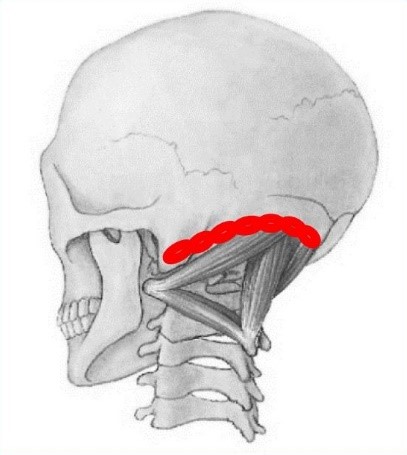

3. Badanie patologicznej czynnościowo aktywności tkankowej na kresie karkowej dolnej poprzez ucisk w okolicach przyczepów mięśni podpotylicznych (ryc. 6).